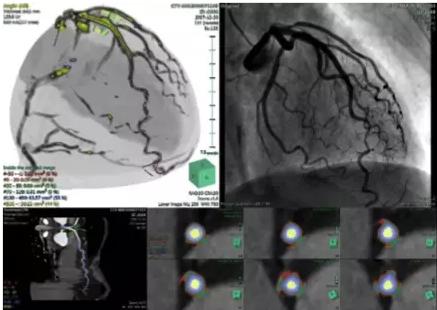

View X-Ray CT & MRI Scans Fast and Easily

Designed for surgeons, Pro Surgical 3D makes it easy to view patient scans quickly. Pro Surgical 3D facilitates the optimal 3D treatment and assessment workflows based on X-ray CT and MRI scans – and best of all, it’s FREE!

High-quality and fast 3D reconstruction and 3D rendering

Performs 3D reconstruction and volume rendering.

Multi-planar slicing.

Side-by-side comparative assessment for pre- and post-operative scans.